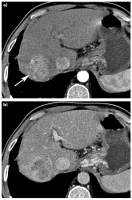

Akute Pankreatitis

Abbildung 7a-b: Akute Pankreatitis. (a) Die kontrastmittelverstärkte CT zeigt wenige Stunden nach Beginn der klinischen Symptomatik eine ödematöse Pankreatitis mit peripankreatischen Exsudatstraßen. Das Pankreasparenchym zeigt noch ein homogenes Enhancement. (b) Vier Tage später zeigt die Kontroll-CT eine ausgedehnte Nekrose im Bereich von Pankreas-Corpus und -Cauda (Pfeile), eine relevante Zusatzinformation zu der Ausgangs-CT unmittelbar nach Beginn der klinischen Symptomatik.